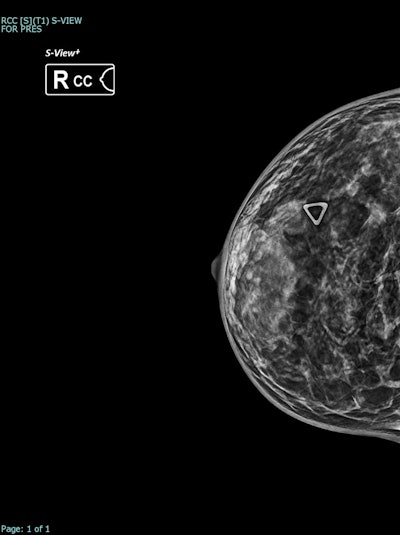

Synthesized 2D mammogram, right breast, craniocaudal (CC) projection of the same patient. No mammographic abnormality is identified. Dense fibroglandular tissue (density grade C) reduces sensitivity.